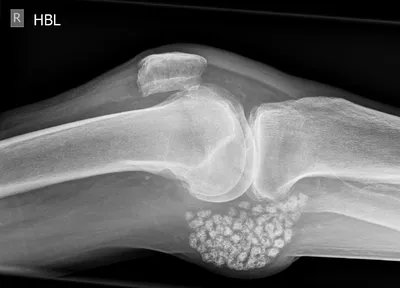

Black PD cartilage sign - chondrocalcinosis in chondral fissure

MRIKneeAxial+2

4/27/2026